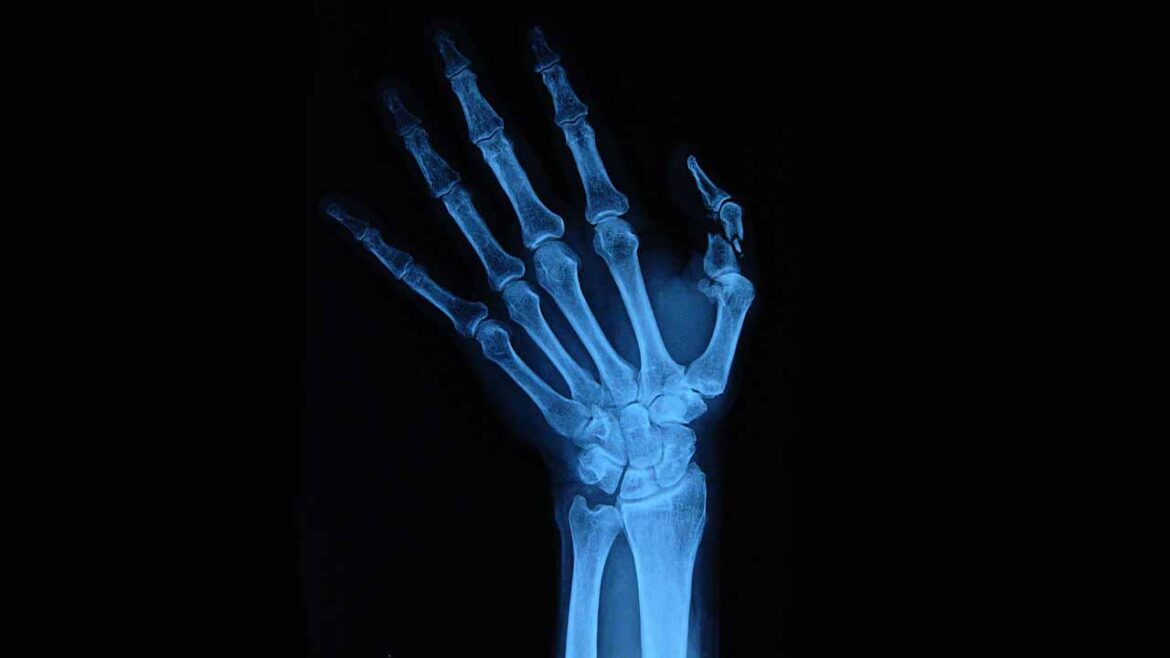

Carpal tunnel syndrome is characterized by burning pain, tingling, or numbness. The hallmark symptoms of classic carpal tunnel syndrome are distributed in the territory of the median nerve, the main nerve that lines the front of your forearm and controls the movement of your hands [3].

This medical condition usually involves the thumb, index finger, middle finger, and part of the ring finger. Essentially, these are the fingers innervated by the median nerve, which is why the pinky finger typically isn’t affected by this medical condition [2]. While some solely experience localized pain and paresthesia affecting the wrists, others struggle with symptoms affecting their entire hand, excluding the pinky [3].

In carpal tunnel syndrome, repetitive hand and wrist movements can lead to the compression and irritation of the median nerve, precipitating the development of characteristic symptoms as mentioned above.